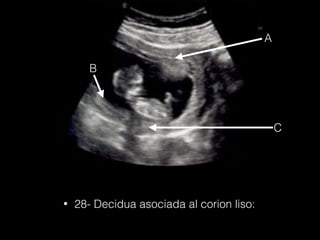

• 28- Decidua asociada al corion liso:

A B C • 28- Deciduaasociada al corion liso: